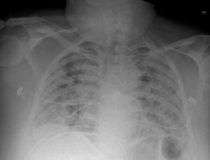

This photo gallery shows the variety of radiological presentations of COVID-19 (SARS-CoV-2) in medical imaging, including computed tomography (CT), radiograph X-rays, ultrasound, echocardiograms and magnetic resonance imaging (MRI). The radiology images show examples of typical COVID pneumonia in the lungs and the numerous complications the virus causes in the body in multiple organs, including the brain, kidneys, heart, abdomen and vascular system.

Ultrasound, especially hand-held ultrasound imaging devices, have become a primary imaging modality for novel coronavirus because of the ease to bag the device and sterilize it after use. CT and mobile X-ray systems are also used as front-line imaging systems for COVID-positive or suspected COVID patients.